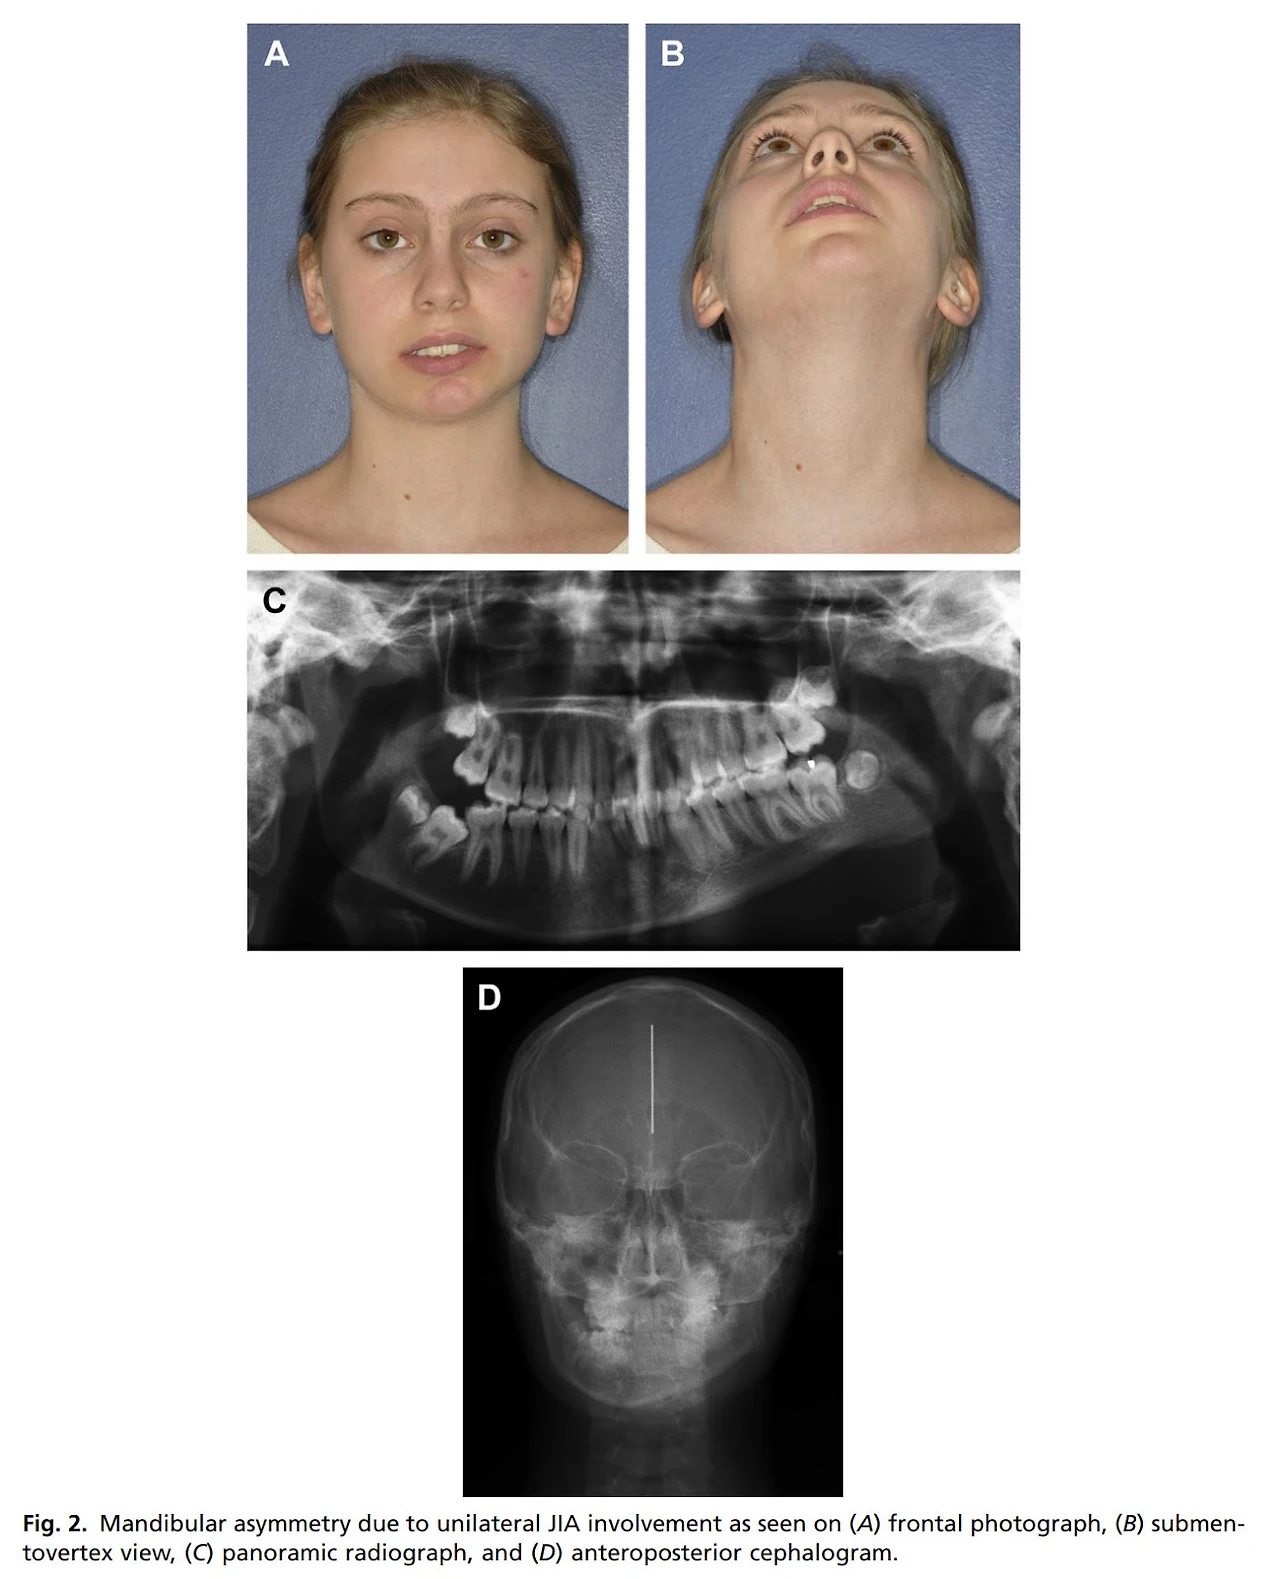

위의 아이는 좌측의 턱관절 염증으로 관절 조직이 손상되고 이로 인해 턱의 중심부위가 관절염증이 있었던 부위로 편위되는 형태의 안면비대칭이 발생하게 되는데, 이런 경우가 생각보다 많습니다.

그림출처: 위와 상동

그림출처: Chouinard, Anne-Frédérique, Leonard B. Kaban, and Zachary S. Peacock. "Acquired abnormalities of the temporomandibular joint." Oral and Maxillofacial Surgery Clinics 30.1 (2018): 83-96.